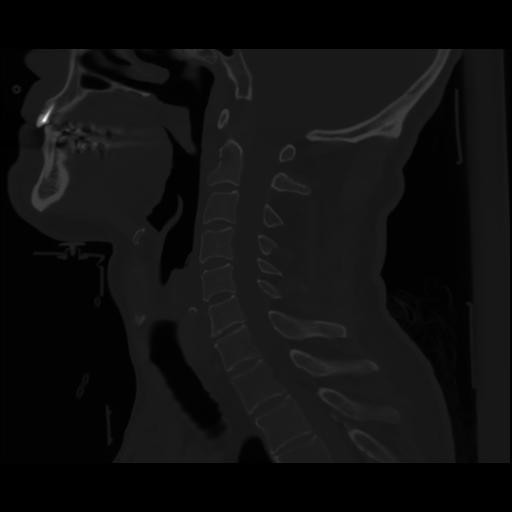

14 P.BLANDAS,,Sagittal,2.000,P.BLANDAS,Sagittal,